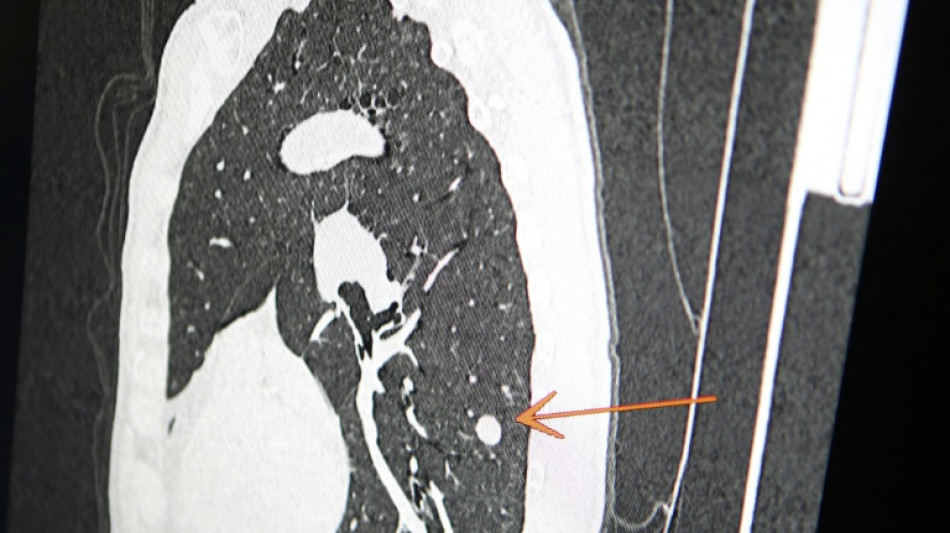

"Usted tiene cáncer", mensaje erróneo y aterrador a cientos de pacientes de una clínica en Inglaterra

"Usted tiene cáncer", mensaje erróneo y aterrador a cientos de pacientes de una clínica en Inglaterra / Foto: © AFP/Archivos

Una clínica del norte de Inglaterra dio un gran susto a cientos de pacientes al enviar el mensaje "diagnóstico: cáncer de pulmón agresivo con metástasis" en lugar de sus buenos deseos de Navidad, informó el diario The Sun el jueves.

El 23 de diciembre a las 15H49, los pacientes de este centro de salud de Askern, cerca de la ciudad de Doncaster, recibieron un mensaje de texto en su teléfono informándoles de este diagnóstico, pidiéndoles que rellenaran los formularios correspondientes y concluyendo: "Gracias".

Según The Sun, entre los destinatarios del mensaje figuraba Chris Reed, un padre de familia de 57 años, que esperaba resultados de análisis para determinar si padecía cáncer de pulmón.